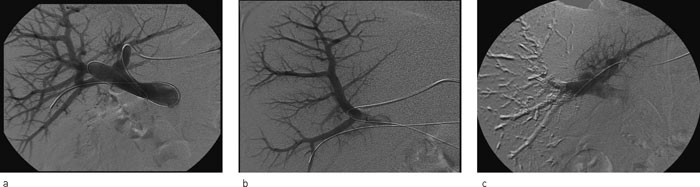

Punksjon av portvenekretsløpet ble utført som intervensjonsradiologisk prosedyre med perkutan transhepatisk tilgang. Hos de fleste ble det gjort innstikk fra venstre side, høyre side ble benyttet hos fire pasienter. En segmentgren av intrahepatisk v. portae ble punktert med finnål under ultralydveiledning. Ved anvendelse av Seldingers teknikk ble en innføringshylse plassert sentralt i portvenen. Ved hjelp av førings- eller mikrokateter ble de enkelte segmentgrenene funnet og embolisert selektivt. Som embolisk agens ble det brukt lim (histakryl og lipiodol), spongostanbiter eller polyvinylpartikler, eventuelt i kombinasjon med coiler (metallspiraler).

Antall prosedyrer har økt siden starten i 2002, og i 2006 ble sju pasienter embolisert. I alt 77 pasienter fikk utført leverreseksjon det året. Vellykket portveneembolisering ble initialt observert hos 16 pasienter (fig 2), to trengte ny prosedyre. Disse to var blitt embolisert med coiler og polyvinylpartikler. Begge ble embolisert på nytt med lim. En pasient måtte laparotomeres samme dag grunnet intraabdominal blødning. Aksidentell punksjon av leverarterien ble påvist og suturert. En annen pasient hadde forbigående gallelekkasje etter aksidentell punksjon av gallegang. Denne ble behandlet med endoskopisk anlagt stent i gallegangen og et perkutant eksternt dren mot subhepatisk beliggende væskeansamling. Tre andre pasienter fikk lette symptomer, som forbigående feber og abdominalsmerter.